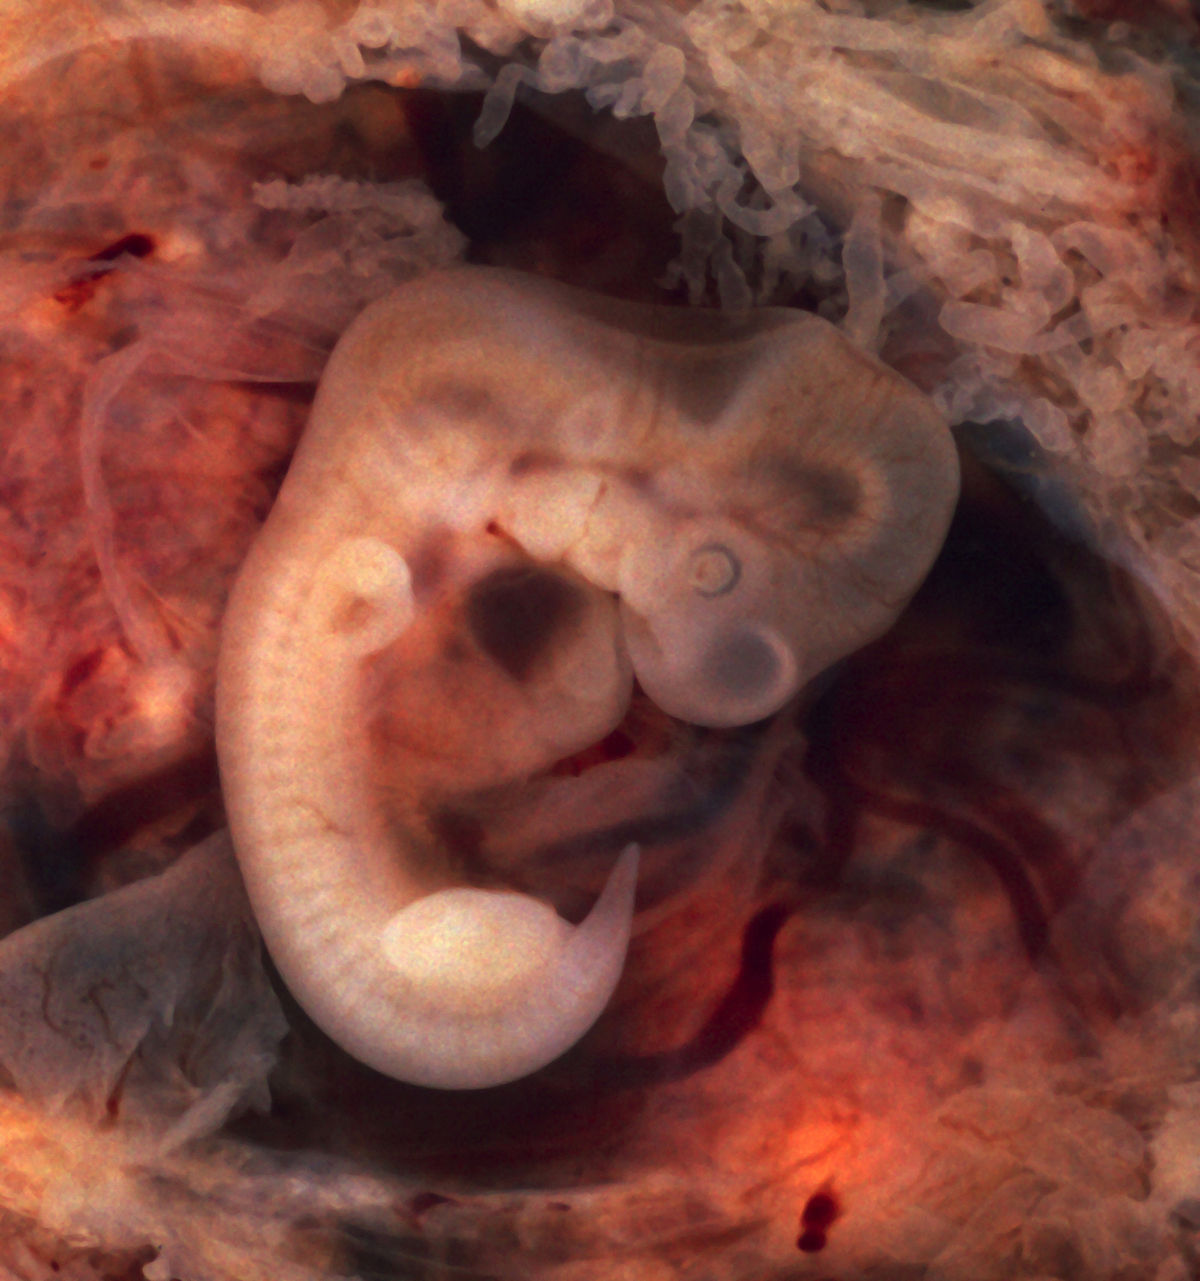

Этапы беременности: иллюстрации и развитие

Раздел: Лаборатория идей